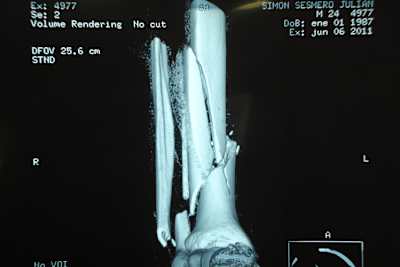

Bereits am Montag unterzog sich der Mapfre-Aspar-Pilot dem dreistündigen Eingriff. Gestern stellte sich heraus, dass die Operationswunde keine Probleme verursachen sollte, nun kann der Suter-Fahrer mit Physiotherapie beginnen. Die OP war aufwändig, weil die Rekonstruktion der zum Teil in sehr kleine Fragmente zersplitterten Knochen komplex war. Nun halten zwei Platten, die mit mehreren Schrauben im Schien- und Wadenbein verankert wurden, die gebrochenen Knochen zusammen.